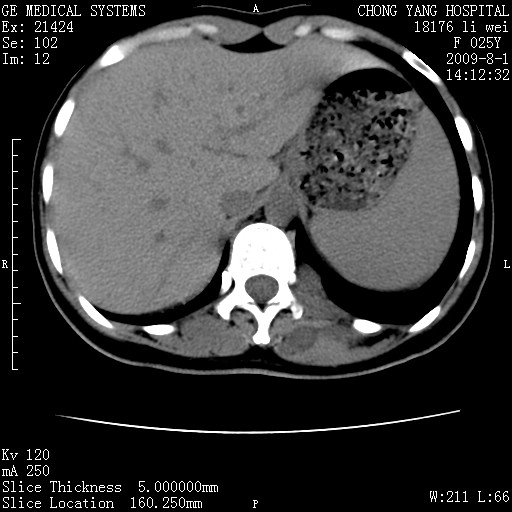

以下是引用pujunzhi在2009-8-1 20:23:00的发言:[br]胸椎旁及背部肌间良性病变,范围广,边界清,沿肌间生长,考虑淋巴管瘤、血管瘤,建议增强扫描。